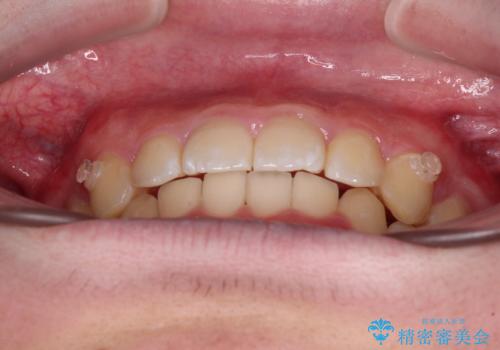

【モニター】斜めに突き出した前歯をインビザラインで改善

- 前方に傾斜した前歯を気にして来院された患者様です。

強く食いしばってしまう癖があり、下顎前歯に押し出されて上顎前歯が前方へ斜めに突き出している状態でした。

IPR(歯と歯の間を削る)を多用して、インビザラインにて矯正治療を行うこととしました。

口元を引っ込めるためのゴムかけを頑張っていただき、満足のいく上顎前歯の傾斜へ改善することができました。